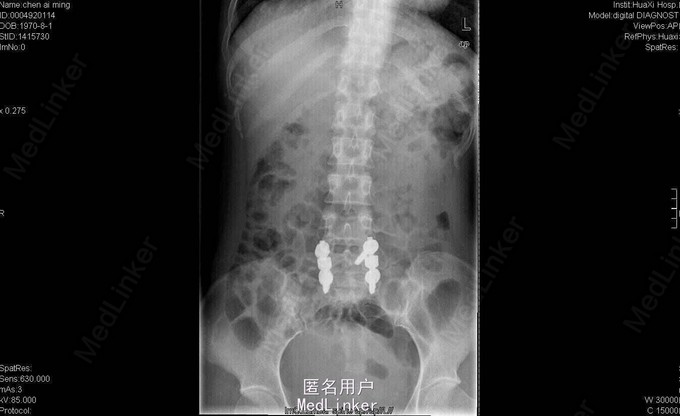

女,40岁2月,因“腰部反复疼痛2+年,加重伴双下肢疼痛、麻木1+年”入院。视:脊柱外观无畸形,皮肤未见红肿、皮疹、破溃、色斑等,无明显包块。触:腰5骶1椎棘突压痛,椎旁肌压痛,无放射痛。腰骶部感觉麻木。双下肢小腿外侧及足背感觉减退,右侧明显,其余肢体感觉正常,肌张力正常。鞍区右侧感觉减退。双下肢足背动脉搏动好。皮温正常。双膝腱减弱,踝阵挛、髌阵挛(-),巴氏征(-),右下肢直腿抬高试验(30°),直腿抬高加强试验(+),左下肢直腿抬高试验(-)。“4”字征阴性。动量:腰部不能屈伸活动,侧弯可,双下肢活动度正常,四肢肌力正常。CT及MRI:腰5骶1椎间盘脱出,腰4-5椎间盘轻度膨出,硬膜囊受压;腰5骨质增生。腰5骶1椎间盘突出症伴小关节退变。双侧椎板开窗腰5骶1椎间盘髓核摘除、内固定术。